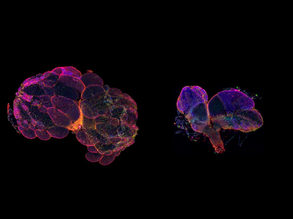

Mini Heart Organoid